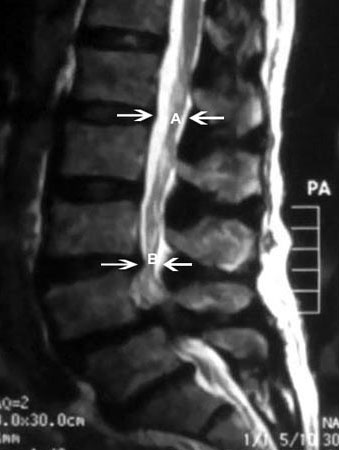

Magnetic resonance imaging of spinal stenosis: (A) demarcates the normal sagittal diameter of the spinal canal. (B) demarcates severe narrowing of the spinal canal